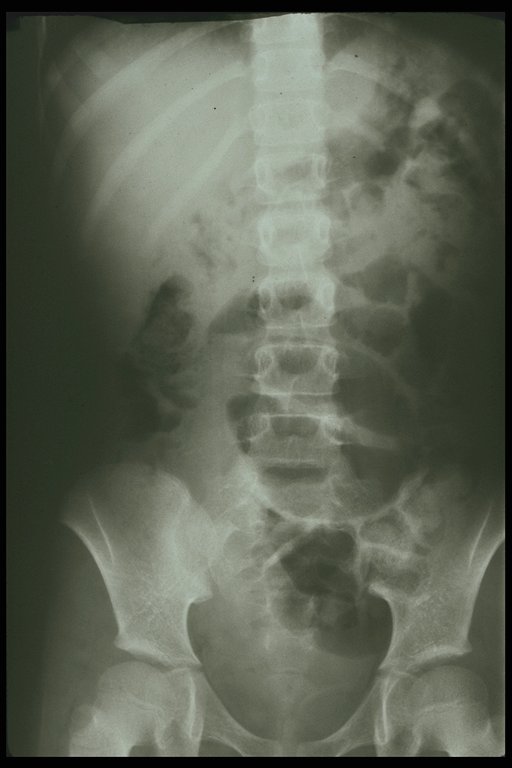

Plain abdominal x-ray shows typical bean-like loop of dilated bowel at left lower abdomen, volvulus of intestine is diagnosed. At operation, volvulus of intestine is found over the Meckel's or omphalomesenteric band